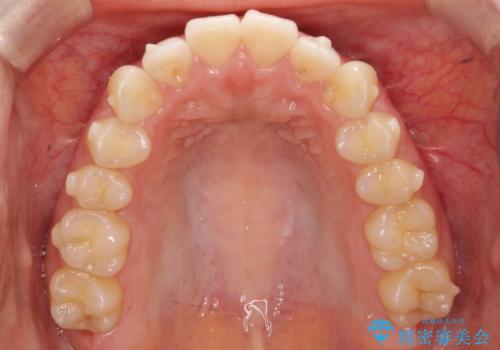

【インビザライン】前歯を下げたい

- 前歯が出ていることを主訴に来院されました。

奥歯を後ろに動かしながらスペースを作ることで、前歯を下げることができ患者さんにも満足していただきました。

治療中に顎間ゴムを使用していただいたおかげで、スムーズに治療を行うことができました。